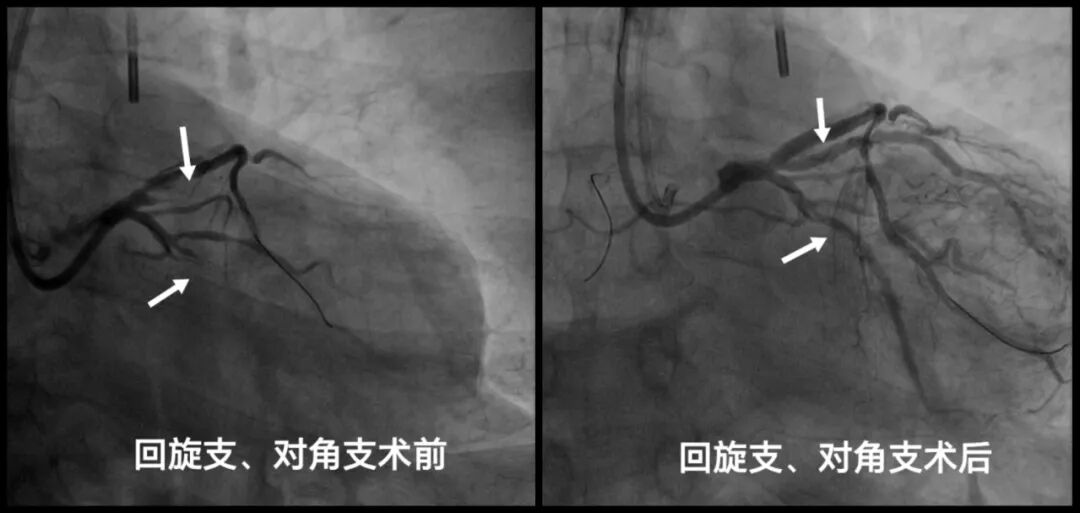

患者为59岁中年男性,2月前因一氧化碳中毒在当地重症监护室治疗,住院期间发现患者心衰指标明显升高,心肌标志物也有轻微升高,遂转入市中心医院。入院后积极改善心功能后完善冠脉造影显示前降支、大对角支、回旋支及右冠状动脉远段均为慢性闭塞,而且其心功能已严重受损,射血分数仅36%,建议首选冠脉搭桥术,心脏大血管外科会诊后认为患者身体弱、基础病多、心功能差、病变复杂,冠脉搭桥风险极高,建议先改善心功能后再评估手术指征。

这场与死神赛跑的手术正式启动。介入导管室护理团队宋静茹、王晴、赵立静、夏欣萍及技师团队王会杰、李鑫提前备台,协调好ECMO、IABP、呼吸机的摆放位置,严阵以待、术中密切配合,东院重症医学科主任宋玮玮带领ECMO小组李昌军、于勇快速熟练为患者植入ECMO+IABP,在ECMO与IABP构筑的“双擎”护航下,向高危复杂病变发起挑战。患者三支血管均为慢性完全闭塞性病变(CTO),手术风险及难度大,在尹波带领下,董国峰、代传芳、董硕主治医师紧密配合,凭借精湛技术与丰富经验,巧妙操控导丝穿越病变,用时1.5小时成功开通4根闭塞血管并精准植入支架,顺利完成冠状动脉的完全血运重建。